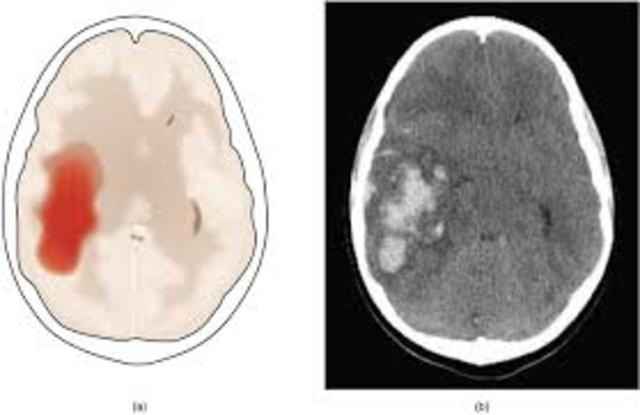

Infarto en divisoria de aguas

Zonas anatómicamente vulnerables situadas entre territorios superpuestos irrigados por las arterias cerebrales mayores (arteria media, anterior y posterior).

-La irrigación sanguínea de zonas distales disminuye, lo que predispone a la isquemia y al infarto de los tejidos.